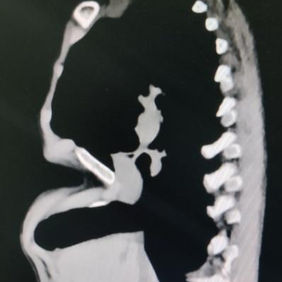

Preoperative Examination

A severe depression is present in the center of the chest wall, with the right edge of the depression forming a ridge-like protrusion. Meanwhile, the edges and bottom of the depression have developed acute angle deformities.